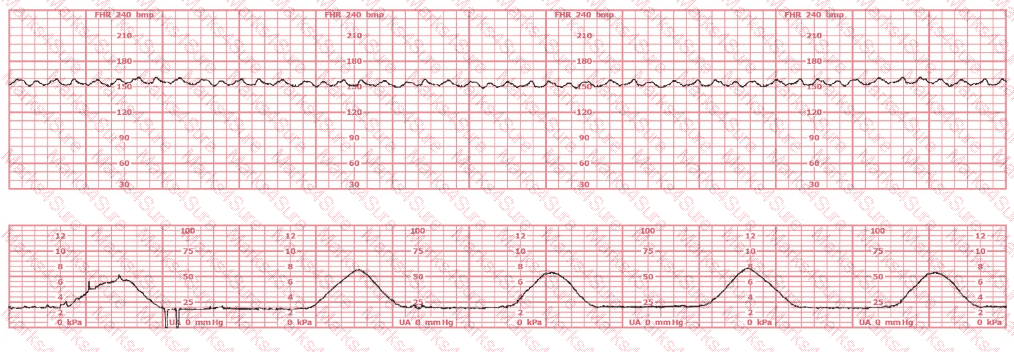

A woman is being induced with oxytocin. The tracing shown is representative of 20 minutes. Based on this tracing, the next step would be to: